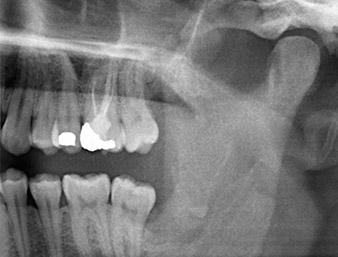

Radiografia panoramica 6 mesi dopo l'osteotomia

Fig. 1: Radiografia panoramica 6 mesi dopo l'osteotomia del dente 38 (LL8): la radix relicta si trova in prossimità del nervo alveolare inferiore.

Il residuo di radice nella regione del dente 38 (LL8) mostrava già stretta vicinanza al nervo alveolare inferiore nell'ortopantomografia. La radice si era spezzata durante l'osteotomia ma non era stata rimossa dal dentista che aveva eseguito l'operazione a causa di dolore intraoperatorio. Per garantire il minor trauma possibile al tessuto, la nuova osteotomia doveva essere eseguita utilizzando un sistema piezochirurgico. Il paziente presentava un'anamnesi non rilevante e non era fumatore.

Un paziente di 26 anni lamentava dolori costanti e parestesia in seguito alla rimozione chirurgica di un dente del giudizio incluso. Le radiografie panoramiche hanno confermato la presenza di un residuo di radice collocato in stretta prossimità del nervo alveolare inferiore.